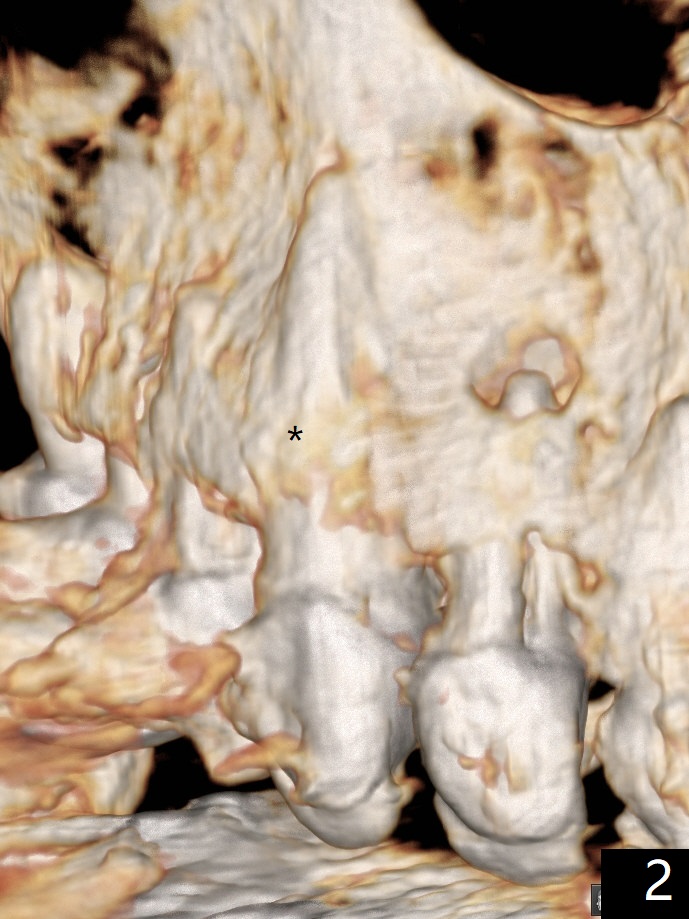

防止拔牙后颊侧骨板萎缩最有效方法是保留部分牙根,例如颊侧(外形象盾牌,简称盾,socket shield (S)),但是制备特别麻烦,尤其是上尖牙。60岁女右上3颊侧骨板隆起(图一至三:*),但是相当狭窄(上下方向),预计强行拔除,势必损失颊侧骨板,造成颊侧塌陷,准备保留盾,如图三红虚线,图六(术后3D长轴断面(十字架:植体))S代表。其实术中试图将整个牙根一起拔除,但是仿佛不行,只好静下心来分根,制备盾,不过困难重重,尤其是除去根尖(防止残余感染),最长外科裂钻似乎达不到根尖,取出后者,颊侧根尖骨板穿孔(图七:箭头)。然后腭侧钻洞(图四),当最后一个钻头保持原位时,在颊侧根尖穿孔处植入粘性骨粉(从牙槽窝口进入,原本粘性骨粉为了修复大面积颊侧缺损用(万一需要强行拔除)),然后才把一段式植体植入(图五),在其余空间填入骨粉,稍微制备基台,制作临时牙冠,最后在牙槽窝开口塞入PRF膜,衬里牙冠,不暂时取出牙冠,衬里相当于临时粘固剂。术后一个月牙根片段和临时牙冠维持良好的牙龈外形(图八,九);术后两个月病人嫌尖牙龈端太尖太长,临时牙冠龈端调整(图十,十一),但愿一个月后龈缘合乎病人期望。